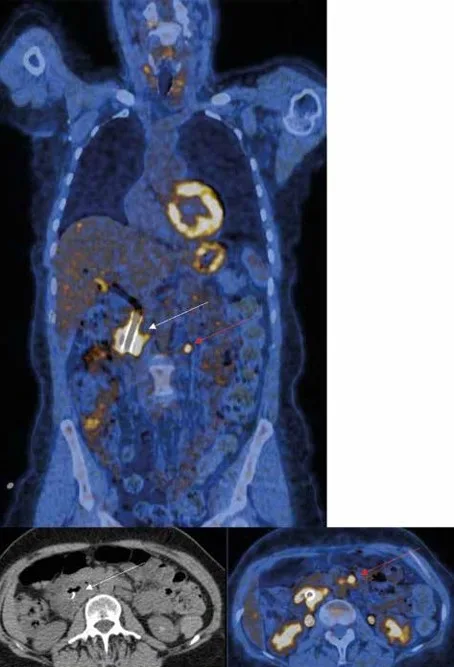

Figure 3 : Patient de 72 ans présentant un adénocarcinome de la tête du pancréas. La TEP réalisée dans le cadre du bilan initial retrouve la masse tumorale pancréatique hypermétabolique intense et une adénopathie hypermétabolique para aortique (flèche rouge).

Bilan d’extension initial

Les performances de la TEP FDG pour l’extension ganglionnaire de l’adénocarcinome du pancréas sont assez moyennes dans la plupart des études disponibles. Certaines études plus récentes ont montré des performances légèrement meilleures de la TEP FDG pour l’évaluation de l’atteinte ganglionnaire à distance du cancer du pancréas (atteinte ganglionnaire cœliaque et latéro-aortique) [46,47] (Figure 3).

La TEP FDG détecte des métastases non soupçonnées sur l’imagerie morphologique réalisée dans le bilan initial d’un adénocarcinome pancréatique [48]. Ce taux de métastases occultes détectées par la TEP FDG s’élève à 30 % des patients dans l’étude rétrospective de Chang [49]. Dans cette étude, parmi les 388 patients ayant un cancer du pancréas localement avancé et qui n’étaient pas métastatiques sur le bilan initial par TDM TAP, 33 % des patients (n = 128) avaient des lésions métastatiques sur la TEP. Le foie était le site métastatique le plus fréquent (56 % des patients), suivi par l’os (21 %), les adénopathies sus claviculaires (18 %), le poumon et la plèvre (13 %), le péritoine (13 %), le médiastin (7.8 %), la cavité pelvienne (5.5 %). La prépondérance des métastases hépatiques dans l’adénocarcinome du pancréas est également soulignée dans une étude de registre totalisant 13 233 patients ayant des métastases au moment du diagnostic [50] ; dans cette série, la distribution des sites métastatiques était, par fréquence décroissante : le foie (77 %), les poumons (20 %), les ganglions à distance (9 %), les os (7 %) et le cerveau (0,7 %). Dans la plupart des études, les performances de la TEP FDG sont très satisfaisantes pour la détection des métastases à distance [49,50], avec des valeurs de sensibilité de 85 % à 89 % et de spécificité de 55 % à 100 %. En revanche, il n’existe pas de données suffisantes ayant comparé la TEP FDG à l’IRM hépatique pour la détection des métastases hépatiques [51]. Par ailleurs, il n’existe pas de données disponibles suffisantes sur les performances de la TEP FDG en fonction du taux de CA 19-9.

La TEP au FDG présente de bonnes performances pour la stadification initiale de l’adénocarcinome pancréatique, en particulier pour l’extension ganglionnaire et métastatique à distance.

En cas de cancer localement avancé et potentiellement résécable sur les données de la TDM, une TEP peut être proposée pour la recherche de métastase(s) non détectée(s) par la TDM et servir de référence lors de l’évaluation de la réponse tumorale au traitement d’induction.